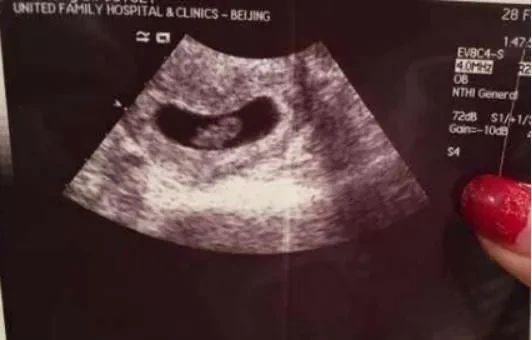

一天上午,马某忍不住吐了起来,面色惨白,她感觉不对,马上到一家私立医院进行体检,发现自己怀孕了,是彭某的骨肉。

马某在激烈的思想斗争中,还是选择了流产,谁知却出了岔子,她因为突发大失血而被送进了医院。

但是,在流产时,可能是生理原因,也可能是医院失误,马某突然失血过多,但不管怎么说,马某的肉身,已经受到了重创,这是无法否认的。

但由于没有进行 DNA 鉴定,马某也没有提供任何证据,证明婴儿是彭某的,而且马某和郭先生的婚姻关系还在继续,所以不能排除郭先生是婴儿的亲生父亲。